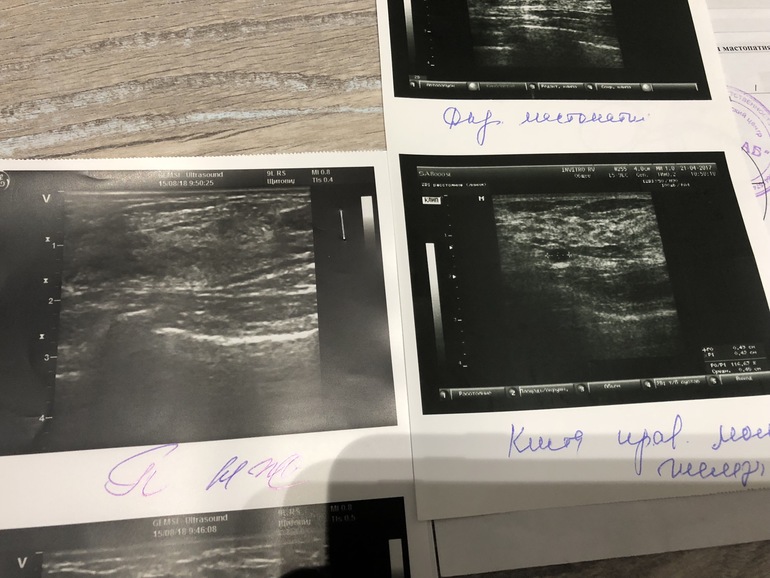

Итог: УЗИ в августе 2018 года -все чисто и там и там ....но кисты у меня были мелкие и всего 2 ... фото загружу для наглядности если будет видно